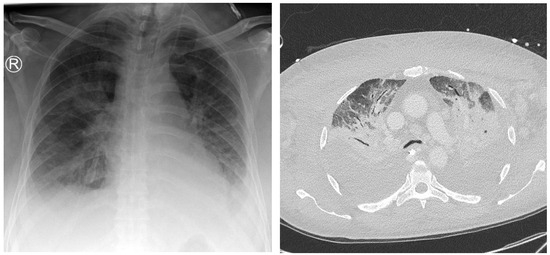

3.3. Infectious Foci in the Context of Preliminary Diagnostics

In the evaluation of the 147 infectious foci identified, 80 (54.4%) had been recognized in at least one previous radiologic examination. A substantial disparity was observed between the anatomical locations: thoracic foci had a higher rate of prior detection, with 68 out of 92 (73.9%) previously reported, whereas only 12 out of 55 abdominal foci (21.8%) had been noted in earlier studies. Of the foci revisited, 41 (27.9% of the total) were confirmed with certainty in at least one previous imaging modality, encompassing 34 thoracic and 7 abdominal foci. In total, 81.3% of these previously diagnosed lesions were identified from the last three preliminary radiographs, yet only 36.9% of these cases resulted in a definitive initial diagnosis (refer to Figure 5).

Computed tomography (CT) proved essential, accurately identifying 55% of all previously diagnosed focal lesions and providing a definite preliminary diagnosis in 72.7% of the cases, affirming its status as the most reliable diagnostic modality. In comparison, despite the limited number of cases (n = 2), preliminary ultrasound examinations delivered definite radiological findings in 50% of the instances. However, two preliminary MRI scans failed to indicate any inflammatory process that was later diagnosed via other modalities.

Figure 5. A 75-year-old patient with a focus of unknown origin and uncertain signs of pneumonia on preliminary radiography. Left: Radiograph showing bilateral opacities in the central and inferior fields. Right: CT scan showing extensive bilateral pulmonary infiltrate and pleural effusion.